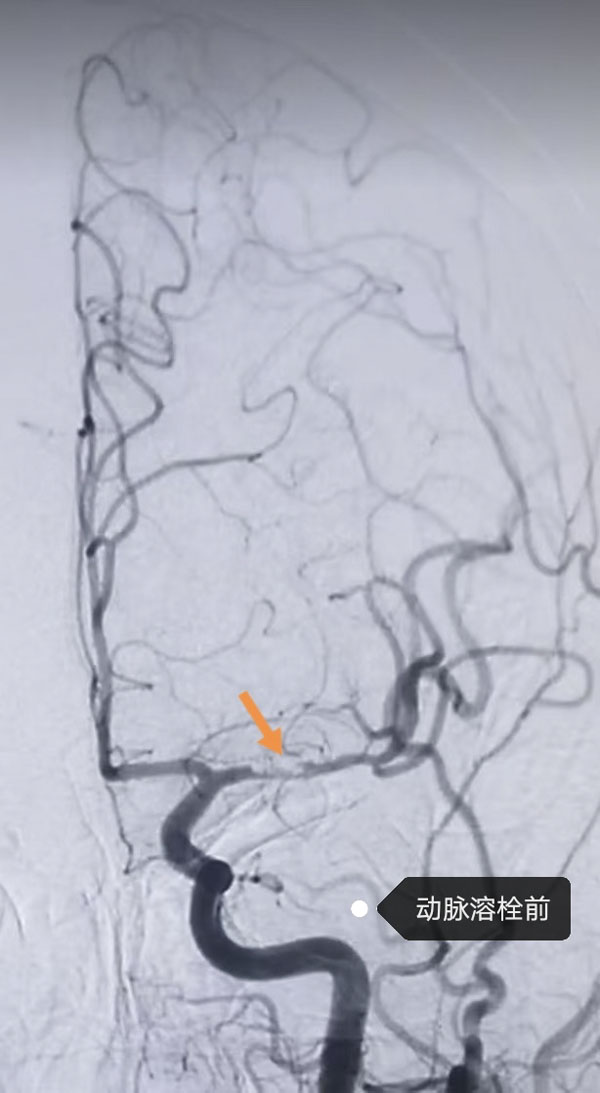

鉴于患者病情危急,接诊医生李晨曦紧急联系介入组李彦青医生启动卒中救治流程,在介入手术室的人员的帮助下,为其实施脑动脉造影术。术中,李彦青发现患者此次发病的责任血管“左侧大脑中动脉”虽存在血流再通,但局部仍为重度狭窄且血栓负荷重,遂决定通过左侧颈内动脉给药以改善局部血供。给药后,复查造影显示狭窄程度明显改善。术后,患者NIHSS评分(神经功能缺损评分)由入院时的8分快速降至3分,言语及右侧肢体活动不利明显改善。一周后出院时,评分进一步降至1分,言语及肢体活动基本恢复正常。